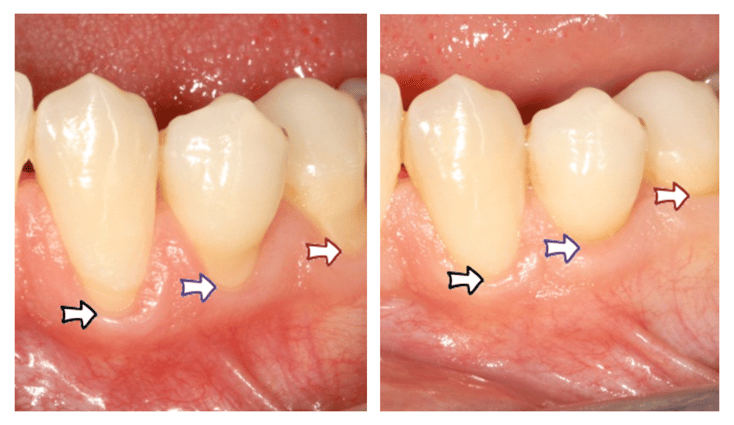

Greffe épithélio-conjonctive en regard de récessions gingivales © ParoSphère

Figure 2 - Greffe épithélio-conjonctive en regard de récessions gingivales © ParoSphère

L'objectif principal de cette technique n'est pas de recouvrir la partie de la racine dénudée mais de constituer un bandeau protecteur de gencive sous la récession. Cette technique n'est donc pas indiquée dans une zone esthétique. En revanche, elle est souvent utilisée pour renforcer la gencive autour de dents qui seront couronnées (Figure 1) ou pour stabiliser des récessions sur des dents du bas, non visibles lors du sourire (Figure 2).